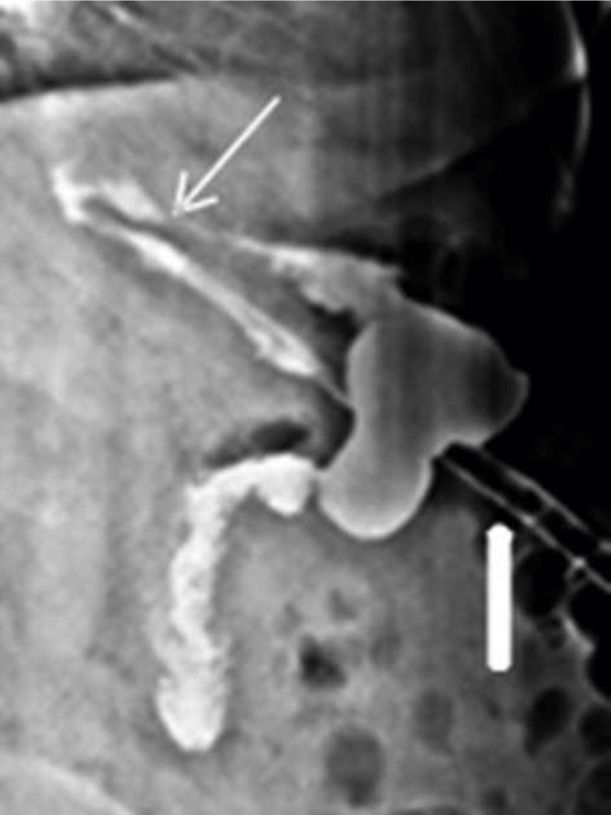

Figura 8

Enfoque oblicuo de EGD en un paciente cursando un mes de postoperatorio,

que muestra estenosis (flecha) de la manga con pasaje filiforme del medio de contraste a dicho nivel(Paciente Nº 18).

c- Estenosis Las estenosis pueden ser precoces (postoperatorio inmediato), las que en general son secundarias a edema, errores técnicos, angulaciones, compresión extrínseca por hematoma o colección peri-gástrica, o tardías (post-operatorio alejado), secundarias a isquemia o fístulas con posterior fibrosis (4,6). Son más frecuentes en la incisura angularis (6). El método de estudio de elección es el EGD con contraste oral hidrosoluble, que muestra la zona estrechez. (6). FIGURA 8